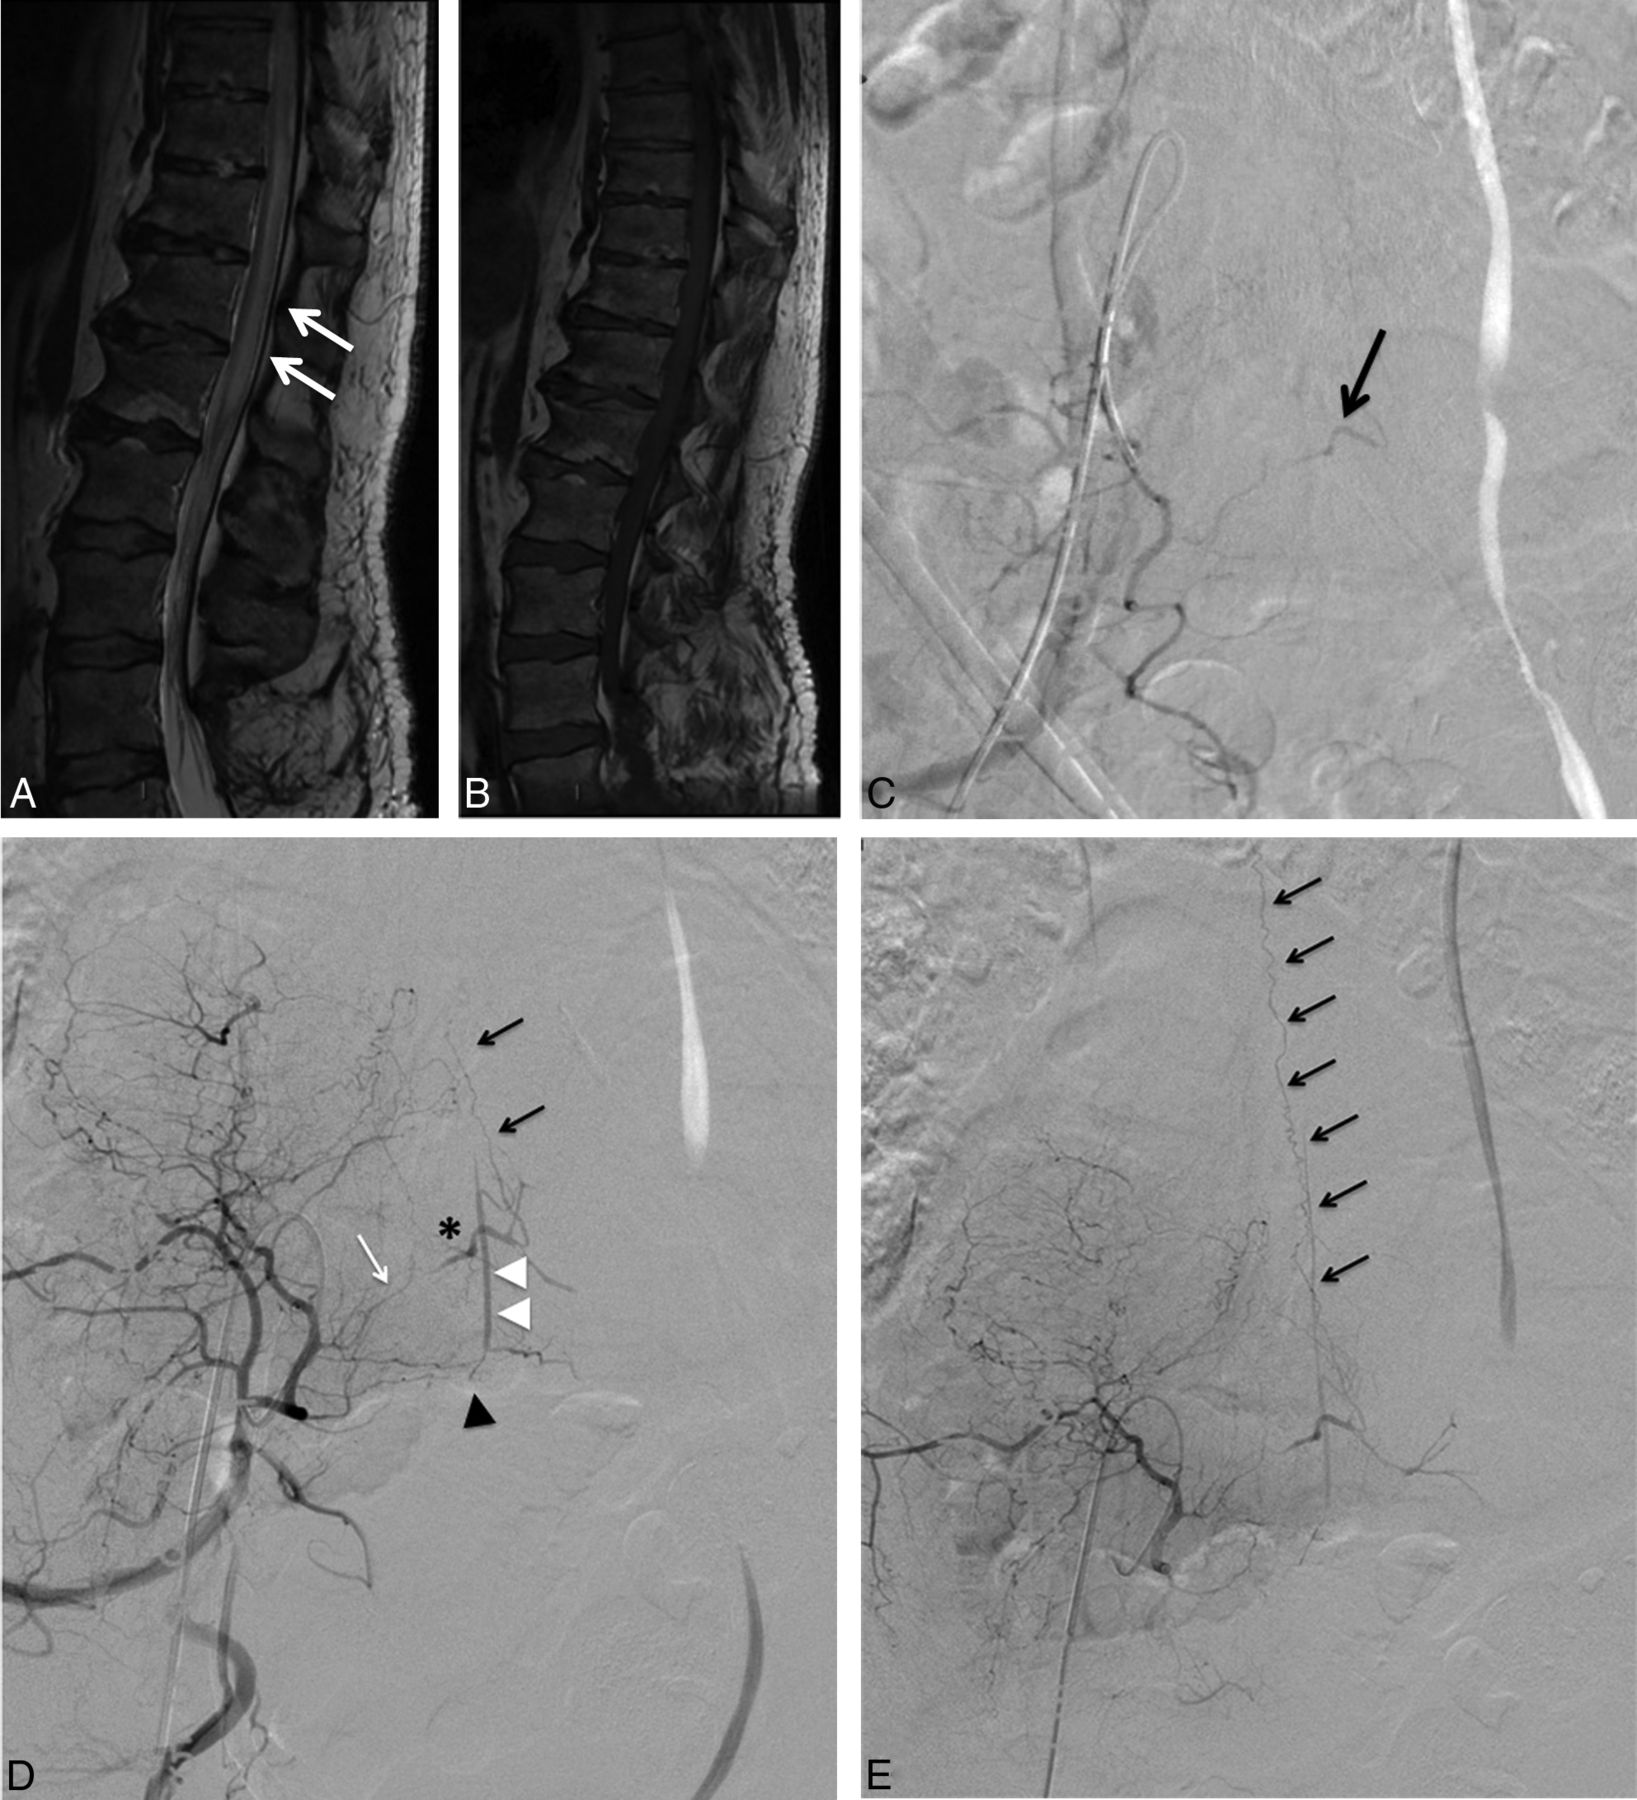

A 56-year-old man presenting with a progressive paraparesis lasting for a few months. Spinal cord MR imaging, sagittal T2-weighted imaging (A), and contrast-enhanced T1WI (B) demonstrate T2 hyperintensity involving the thoracolumbar spinal cord and the conus medullaris (A, white arrows), which may be suggestive of a SDAVF. However, no perimedullary vein enhancement on contrast-enhanced T1WI is seen (B). A first digital subtraction angiography was performed with a negative result for SDAVF (not shown). However, the internal iliac arteries were not catheterized during this first spinal DSA. A second sDSA was performed 3 months after the first one (C). The right internal iliac artery was catheterized, but too proximally. The sDSA findings were interpreted as normal. A second look revealed a possible fistula fed by the right superior lateral sacral artery (LSA) (C, arrow). D and E, Right internal iliac artery DSA in an anteroposterior projection. D, Early phase. E, Late phase, large FOV. The tip of the catheter is located close to the origin of the right LSA. The presence of a SDAVF is confirmed, fed by the right superior LSA (D, white arrow). The shunt point is located along the right S1 nerve root (asterisk) with low-flow ascending venous drainage (D and E, black arrows). Note the pre-anastomosis between a branch of the LSA (D, black arrowhead) and the medial sacral artery (D, white arrowheads).